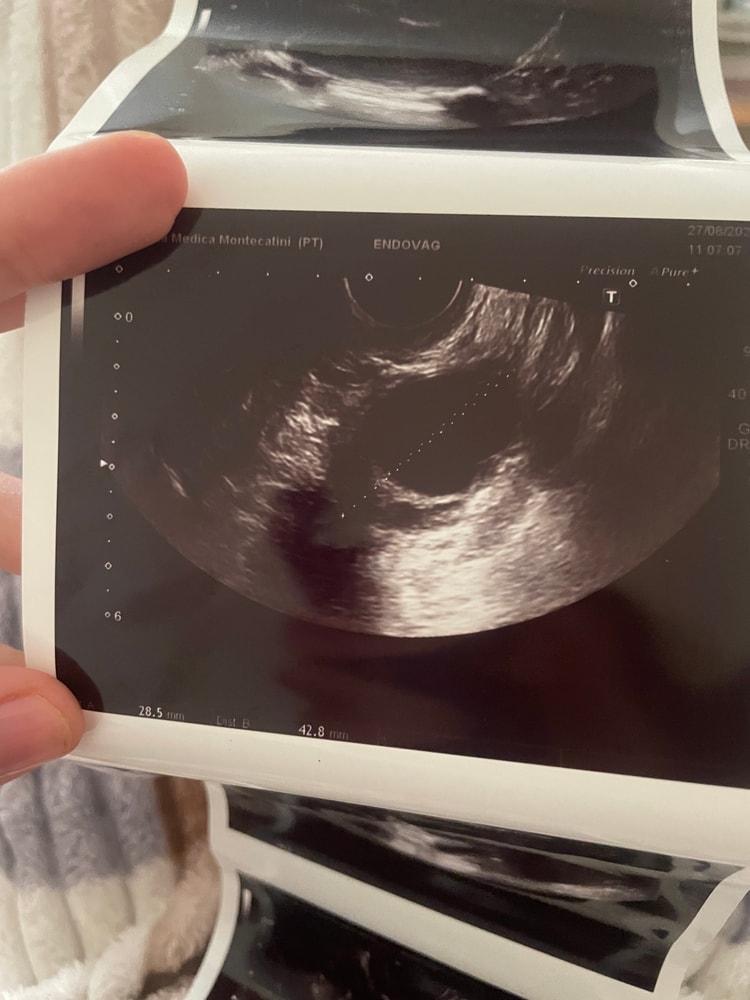

Девочки, подскажите, пожалуйста. Была на УЗИ и мне сказал врач что и на правом и налево яичники есть кисты ( 28*24 мм и 28*36 ) . Спросив какого они типа - он сказал что нужно наблюдать , пока Это не страшно , могут сами пройти . Вопрос такой , с кистами забеременеть нереально ? Они влияют на О ??? Хоть по графику бт она бывает, но …. капец ,аж 2 кисты 😭🤷🏻♀️

p.s. Сегодня поднялась бт , разболелась голова и появились выделения как обычно после О . Значит она случилась , и среди этих «кист» как минимум 1 доминантный фоликул был . Посмотрим дальше.